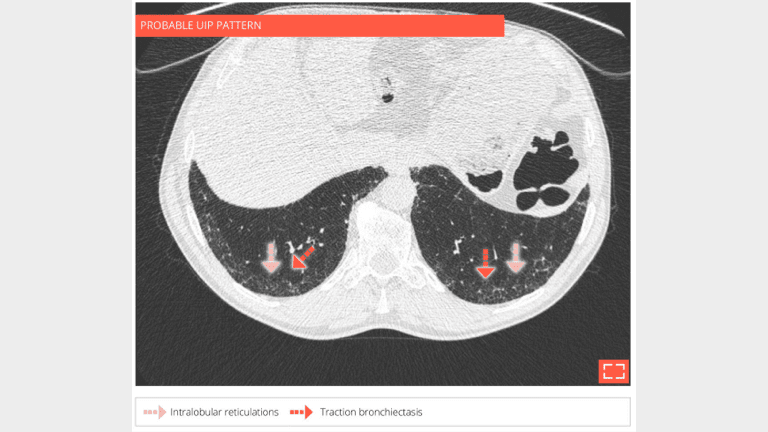

• Isolated and subtle subpleural intralobular reticulations and traction bronchiectasis of the 2 lower lobes.

• No ground-glass opacity or honeycombing.